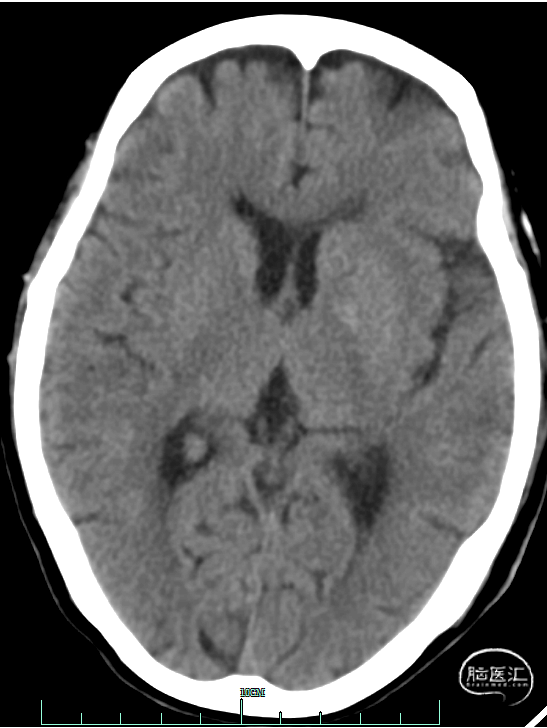

术前影像资料